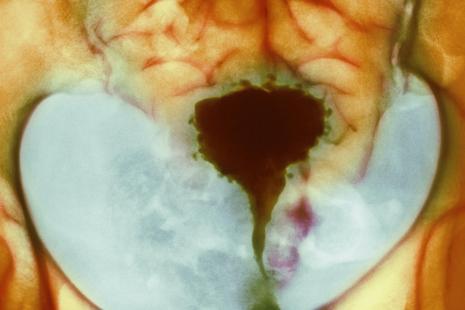

« La maladie est provoquée par une chute de la muqueuse utérine dans le muscle, suivie de contractions qui envoient les cellules endométriales dans les trompes voire dans d’autres organes », rappelle le radiologue. Ces cellules peuvent rester localisées dans le muscle utérin (adénomyose), toucher le péritoine (endométriose superficielle), former un kyste au niveau de l’ovaire (endométriose ovarienne) voire former de nodules qui atteindront d’autres organes comme la vessie, le rectum, le côlon, le diaphragme ou la paroi pelvienne (endométriose profonde). De façon plus rare, ces nodules peuvent toucher l’appareil respiratoire et ophtalmique. « Dans 30 à 40 % des cas, les femmes connaissent des problèmes d’infertilité, généralement avec les formes sévères », précise le médecin.

« En consultation, les signes cardinaux qui doivent alerter sont les dysménorrhées, les dyspareunies profondes et l’infertilité », souligne le Dr Petit. Le diagnostic doit reposer sur un interrogatoire « précis et attentif » suivi d’une imagerie effectuée par un radiologue référent ayant une bonne connaissance de l’endométriose et de son diagnostic, si possible en centre expert. « À défaut, une IRM pourra être effectuée », précise le spécialiste.